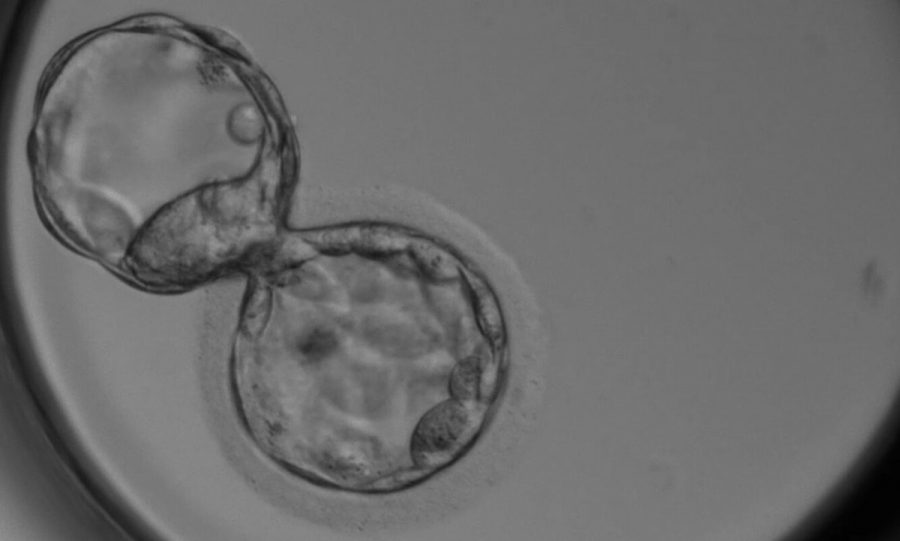

Sàng lọc phôi là một kỹ thuật phân tích gen di truyền trước khi thực hiện chuyển phôi. Thông qua sự phân tích này mà bác sĩ có thể hỗ trợ các cặp vợ chồng có thể lựa chọn những phôi có chất lượng tốt nhất về gen di truyền trước khi chuyển phôi vào buồng tử cung của người mẹ.

Trong quá trình phôi thai đang hình thành và phát triển, các tế bào sẽ phân chia theo cấp số nhân. Nếu quá trình phân chia đó gặp vấn đề, số nhiễm sắc thể (mỗi tế bào có 23 cặp nhiễm sắc thể gồm 22 cặp nhiễm sắc thể thường và 1 cặp nhiễm sắc thể giới tính) phân chia không đúng hoặc không phân ly sẽ gây ra sự sai sót, được gọi là đột biến dị bội. Quá trình này có thể gây ra một số vấn đề như sau:

Cho nên việc sàng lọc phôi thai sẽ giúp các cặp vơ chồng chọn lọc được các phôi thai khỏe mạnh trước khi đặt vào buồng tử cung, sẽ làm tăng khả năng mang thai và phôi làm tổ, em bé được khỏe mạnh. Tuy nhiên, chỉ làm sàng lọc phôi tiền làm tổ nếu có sự chỉ định của bác sĩ.